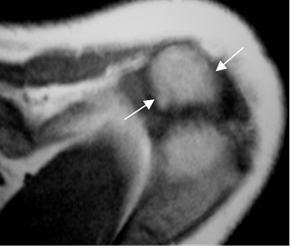

Fig 83. Cambios degenerativos en articulación acromioclavicular.

A y B: Ecografía coronal. Osteofitos en la articulación acromioclavicular (Flechas delgadas), con la presencia de líquido (Flechas gruesas) por cambios degenerativos.